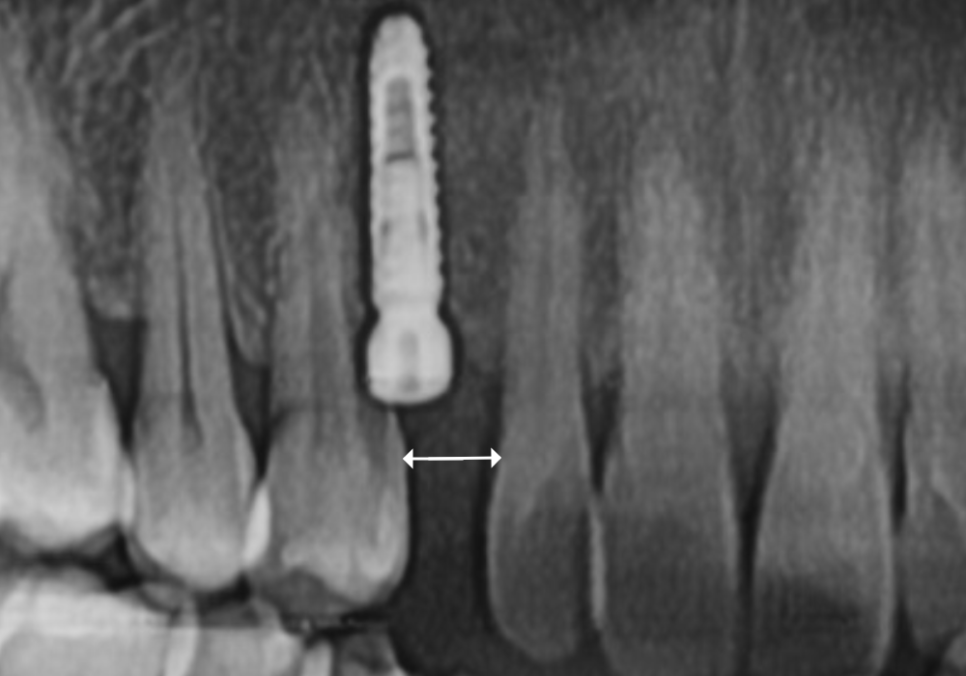

다행히 유치 주변의 뼈는 아직 임플란트를

충분히 고정할 수 있을 만큼 튼튼해서,

유치를 발치하는 당일,

별도의 뼈이식 없이

임플란트를 식립해드렸습니다.

수술 후 3개월 뒤,

임플란트가 뼈와 완벽히 굳은 것을 확인하고